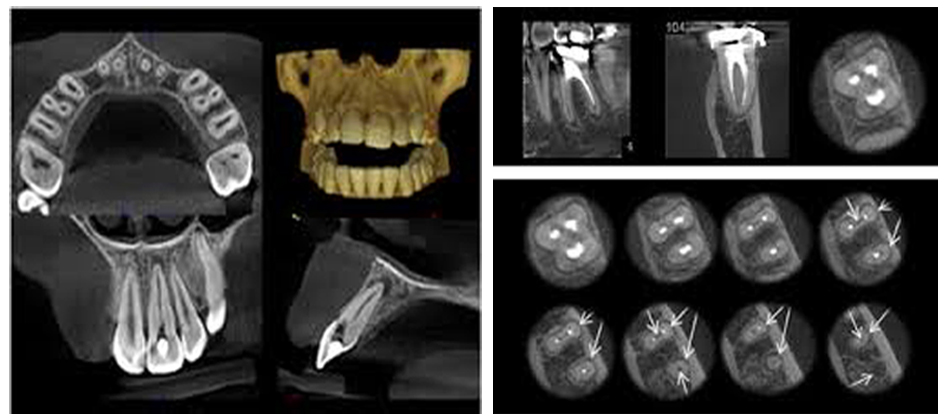

Din cele prezentate mai sus observam ca pentru un tratament endodontic corect, examenul radiologic este indispensabil si obligatoriu. Cel mai important avantaj pe care il aduce radiografia digitala pentru tratamentul endodontic este faptul ca prin intermediul softurilor dedicate se pot face masuratori pentru stabilirea lungimii de lucru, dar si posibilitatea prelucrarii imaginii in vederea vizualizarii mai exacte a porțiunilor de interes terapeutic, cum putem observa in imaginile de mai jos:

Pentru cazurile mai dificile cu dinți a caror anatomie este deosebita, ori prezinta obstacole pe traiectul canalelor radiculare, sau prezinta suspiciunea prezenței unor fisuri sau fracturi nedetectabile la microscop sau la radiografia retroalveolara, se utilizeaza ca metoda de investigare CBCT-ul (Computerul Tomograf cu Fascicul Conic), care este o tehnologie de ultima generație in domeniul imagisticii ce permite vizualizarea in plan tridimensional a zonelor scanate. Folosind un fascicul conic de raze X, scanerul CBCT are nevoie de o unica rotație in jurul pacientului pentru a prelua sute de imagini ale zonei de interes, acestea fiind apoi reconstruite cu ajutorul unui software de imagistica, in vederea obținerii modelului virtual 3D al pacientului, model ce ne permite vizualizarea din toate unghiurile a zonei investigate, implicit si a leziunilor prezente la acest nivel: